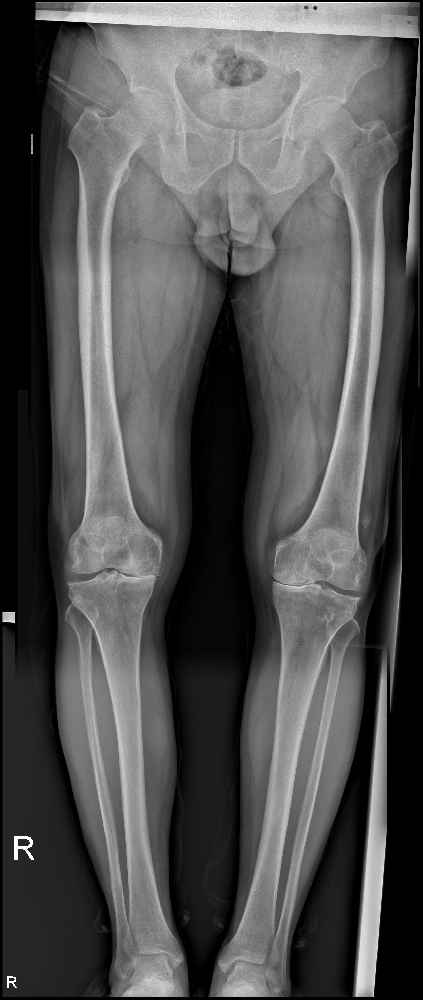

馬廣良的堅(jiān)持和決心打動(dòng)了醫(yī)院的醫(yī)生和護(hù)士,他們給予她最貼心的照顧和專業(yè)的建議。經(jīng)過(guò)一系列完善的檢查,醫(yī)生發(fā)現(xiàn)她的左膝關(guān)節(jié)內(nèi)側(cè)已經(jīng)受到嚴(yán)重的損傷,需要進(jìn)行手術(shù)治療,以恢復(fù)她的正常生活。

手術(shù)是一次考驗(yàn)醫(yī)生技術(shù)和馬廣良意志力的時(shí)刻。馬廣良選擇了手術(shù),并接受了左膝關(guān)節(jié)內(nèi)側(cè)活動(dòng)平臺(tái)單髁置換術(shù)。手術(shù)雖然對(duì)她來(lái)說(shuō)充滿了一份未知,但她相信這將是獲得新生的關(guān)鍵一步。